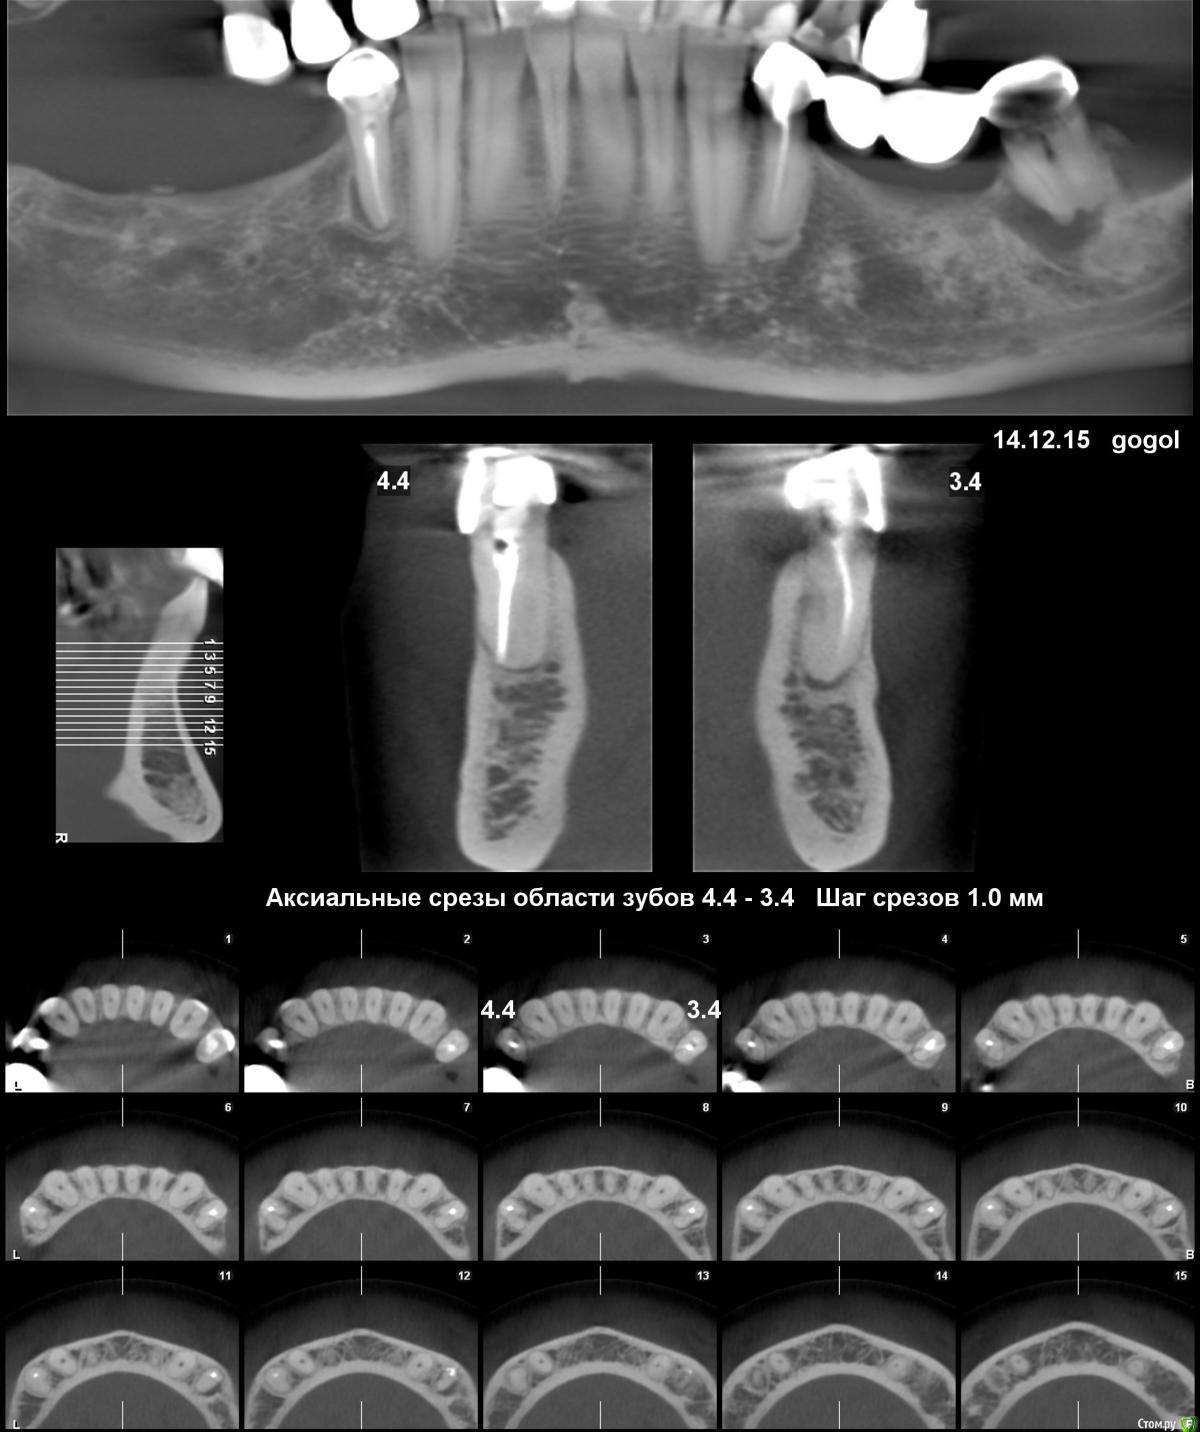

malin Опубликовано 30 января, 2016 Поделиться Опубликовано 30 января, 2016 Здравствуйте! Прошу совета. Предстоит костная пластика и последующая имплантация. Вопрос по обеим нижним "четвёркам" - лечить или удалять? Они не болят, вообще не беспокоят, но хирургу не нравятся. С левой стороны (где мост) настаивает на удалении, справа - не так категоричен, но говорит, что вокруг корней разрежение костной ткани, если что пойдёт не так - пеняйте потом на себя. По "семёрке" вопроса нет, её однозначно удалять. Ссылка на комментарий

Гарриевич Опубликовано 30 января, 2016 Поделиться Опубликовано 30 января, 2016 мост снять, сделать прицельный снимок и только потом решатьс правой стороны лечить 95% 1 Ссылка на комментарий